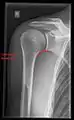

Imaging

Imaging of the shoulder includes ultrasound, X-ray and MRI, and is guided by the suspected diagnosis and presenting symptoms.

Conventional x-rays and ultrasonography are the primary tools used to confirm a diagnosis of injuries sustained to the rotator cuff. For extended clinical questions, imaging through Magnetic Resonance with or without intraarticular contrast agent is indicated.

Hodler et al. recommend starting scanning with conventional x-rays taken from at least two planes, since this method gives a wide first impression and even has the chance of exposing any frequent shoulder pathologies, i.e., decompensated rotator cuff tears, tendinitis calcarea, dislocations, fractures, usures, and/or osteophytes. Furthermore, x-rays are required for the planning of an optimal CT or MR image.[23]

X-ray

Projectional radiography views of the shoulder include:

- AP-projection 40° posterior oblique after Grashey

The body has to be rotated about 30 to 45 degrees towards the shoulder to be imaged, and the standing or sitting patient lets the arm hang. This method reveals the joint gap and the vertical alignment towards the socket.[24]

- Transaxillary projection

The arm should be abducted 80 to 100 degrees. This method reveals:[24]

- The horizontal alignment of the humerus head in respect to the socket and the lateral clavicle in respect to the acromion

- Lesions of the anterior and posterior socket border, or of the tuberculum minus

- The eventual non-closure of the acromial apophysis

- The coraco-humeral interval

- Y-projection

The lateral contour of the shoulder should be positioned in front of the film in a way that the longitudinal axis of the scapula continues parallel to the path of the rays. This method reveals:[24]

- The horizontal centralization of the humerus head and socket

- The osseous margins of the coraco-acromial arch and hence the supraspinatus outlet canal

- The shape of the acromion

This projection has a low tolerance for errors and, accordingly, needs proper execution.[24] The Y-projection can be traced back to Wijnblath’s 1933 published cavitas-en-face projection.[25]

- CR. shoulay film.